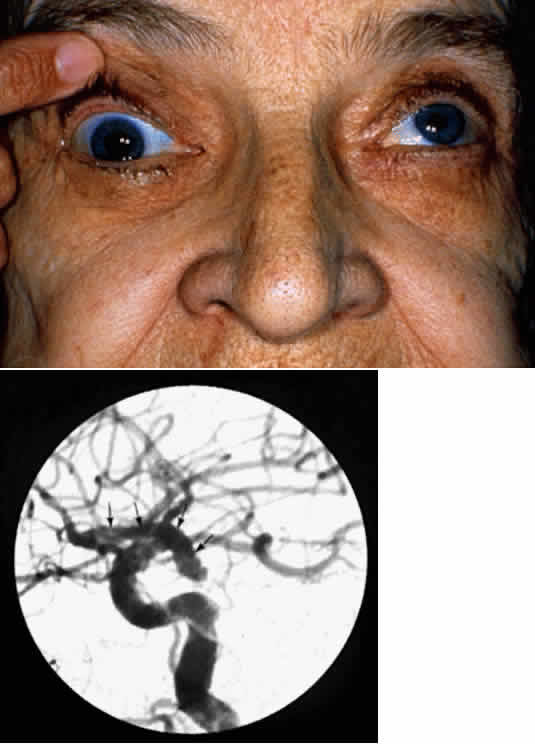

Compression of the oculomotor nerve from a tumor or aneurysm usually causes external ophthalmoplegia, in conjunction with a reduced pupillary light reflex and reduced accommodation, as a result of the superficial location of the autonomic nerves in relation to the motor nerves. Aneurysms of the posterior communicating artery, which is located just medial to the oculomotor nerve as it exits the midbrain, commonly compress the nerve at its medial aspect, causing impairment or loss of pupillary constriction (Fig. 16). In contrast, ischemia of the oculomotor nerve at its subarachnoid location usually spares pupillary and accommodative function, but results in an external ophthalmoplegia that usually recovers within 8 to 12 weeks.

Fig. 16. Photos showing right pupil involving oculomotor nerve palsy (top) in a patient with a posterior communicating artery aneurysm (bottom).